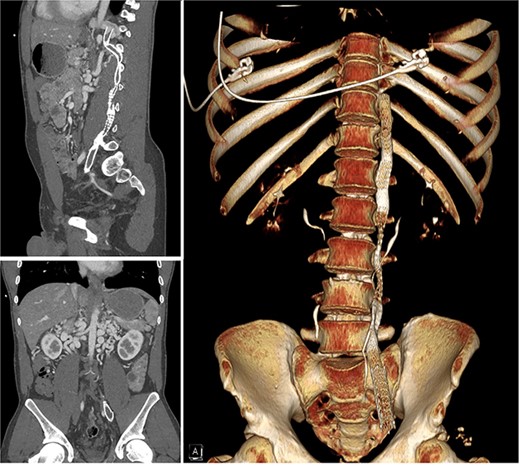

A 30-year-old male presented to medical attention with left lower extremity swelling and leg pain in October 2022 following a long flight. A thorough workup was consistent with extensive deep vein thrombosis (DVT)s in the left external, internal, and common iliac veins, and the thrombus continued into a large left lumbar collateral. The IVC and the high left common iliac vein were atretic (Fig. 1) with large, tortuous collaterals. He was also found to have severe mitral regurgitation. The patient was treated with mechanical thrombectomy and started on Apixaban. The patient underwent stent-grafting of his retroperitoneal collaterals to the level of the left external iliac artery. These stents were compromised (compressed or occluded) by the time the patient was evaluated for his MV repair in October 2023 when he was symptomatic and optimized for repair. Pre-op echocardiogram (ECHO) demonstrated bi-leaflet MV prolapse with myxomatous changes and severe MV regurgitation. A robotic approach was deemed appropriate for his case.

Computer tomography scan showing chronic occlusion of the infra-hepatic IVC and common iliac veins.